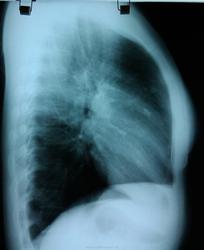

На боковом интересные "очаговые" тени...

Очаговые тени в переднем сегменте. В дифряд - мальформация.

Прямая и боковая разнятся (на мой взгляд) за счет суммации изображений обоих легких на боковой рентгенограмме. При всем уважении к линейной ТГ - в конкретном случае (молодая женщина, визуальный рост "очага", относительно малые его размеры, три года наблюдения, доверие клиницистов к КТ) сразу постарался бы найти возможность для КТ.

Обработанные снимки.